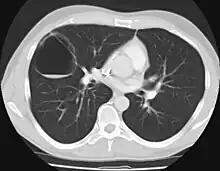

CPAMs are classified into three different types based largely on their gross appearance. Type I has a large (>2 cm) multiloculated cysts. Type II has smaller uniform cysts. Type III is not grossly cystic, referred to as the "adenomatoid" type. Microscopically, the lesions are not true cysts, but communicate with the surrounding parenchyma. Some lesions have an abnormal connection to a blood vessel from an aorta and are referred to as "hybrid lesions."

The earliest point at which a CPAM can be detected is by prenatal ultrasound. The classic description is of an echogenic lung mass that gradually disappears over subsequent ultrasounds. The disappearance is due to the malformation becoming filled with fluid over the course of the gestation, allowing the ultrasound waves to penetrate it more easily and rendering it invisible on sonographic imaging. When a CPAM is rapidly growing, either solid or with a dominant cyst, they have a higher incidence of developing venous outflow obstruction, cardiac failure and ultimately hydrops fetalis. If hydrops is not present, the fetus has a 95% chance of survival. When hydrops is present, risk of fetal demise is much greater without in utero surgery to correct the pathophysiology. The greatest period of growth is during the end of the second trimester, between 20–26 weeks.

A measure of mass volume divided by head circumference, termed cystic adenomatoid malformation volume ratio (CVR) has been developed to predict the risk of hydrops. The lung mass volume is determined using the formula (length × width × anteroposterior diameter ÷ 2), divided by head circumference. With a CVR greater than 1.6 being considered high risk. Fetuses with a CVR less than 1.6 and without a dominant cyst have less than a 3% risk of hydrops. After delivery, if the patient is symptomatic, resection is mandated. If the infant is asymptomatic, the need for resection is a subject of debate, though it is usually recommended. Development of recurrent infections, rhabdomyosarcoma, adenocarcinomas in situ within the lung malformation have been reported.[4]